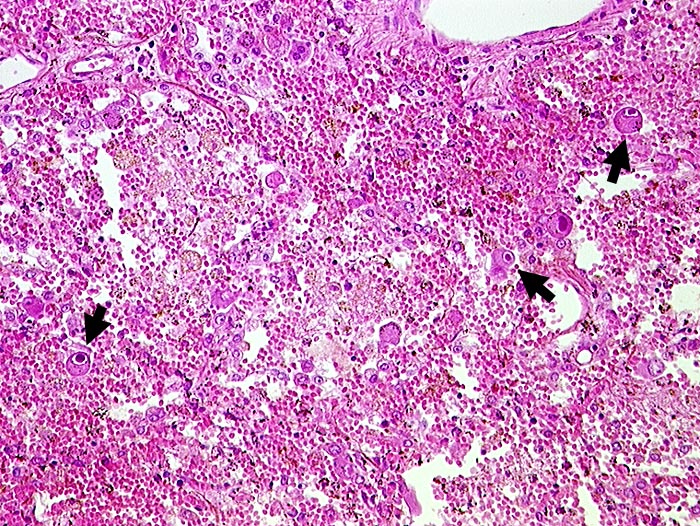

PathoPic – image database / PathoPic ID 216 - CMV (Zytomegalie) Pneumonie

CMV (Zytomegalie) Pneumonie

Entzündung infektiös

Lunge

► Virale Kerneinschlüsse mit Halo in Pneumozyten (sogenannte Eulenaugenzellen). Intraalveoläre Hämorrhagie.

HIV positiv seit 5 Jahren. Nachweis von zytomegalen Zellen im Hirn, in der Lunge, im Gastrointestinaltrakt, den Nieren und der Nebenniere. Zusätzlich bakterielle Pneumonie.